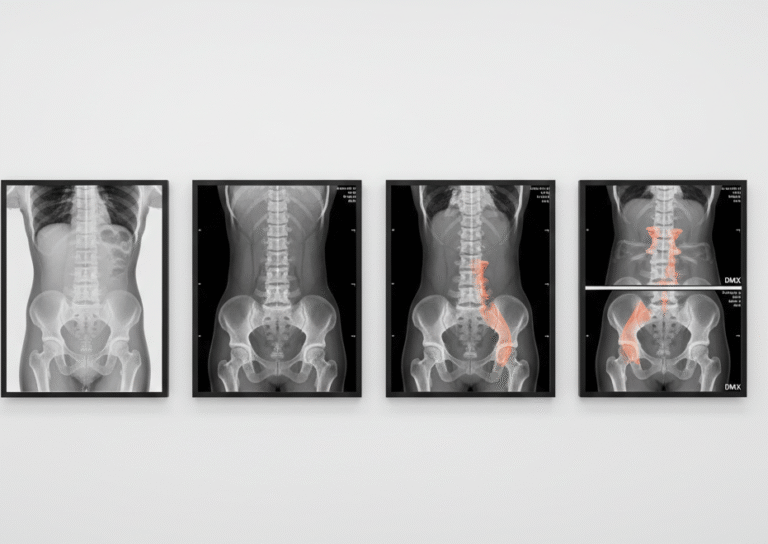

Digital Motion X-Ray: Seeing the Spine in Action

What DMX does differently at DMX Miami:

- Uses fluoroscopic video X-ray to record the spine during movement.

- Evaluates the cervical, thoracic, or lumbar spine while you perform gentle, guided motions.

- Measures abnormal translation and angulation between vertebrae.

- Helps reveal ligament injuries and instability that only appear when the spine is moving.

DMX doesn’t replace MRI or CT. Instead, it complements them by answering a different question:

“What happens when my spine actually moves?”